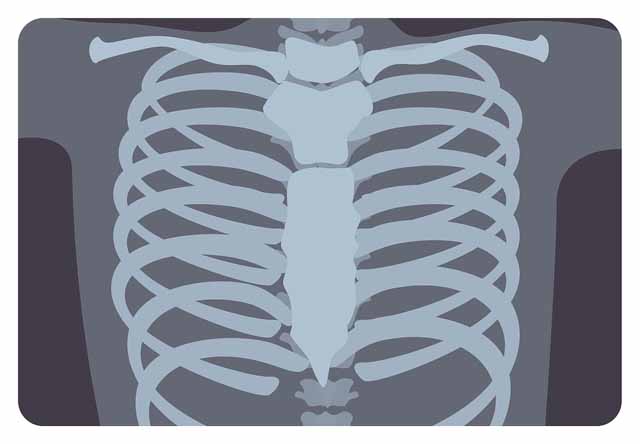

숨 쉴 때 곤란함과 갈비뼈, 가슴의 압박감, 답답함 등은 물론 잦은 기침, 쌕쌕거리는 숨소리 등이 있다고 한다면 폐 질환을 생각해 보아야 하는데 엑스레이 등으로 폐의 컨디션을 체크해 보는 것이 중요 해요 특히나체중의 감소와 같이 과도한 기침이 3주 이상 진행되었을 경우이라면 폐결핵, 기흉, 폐암 등을 확인해 볼 필요가 있어요.